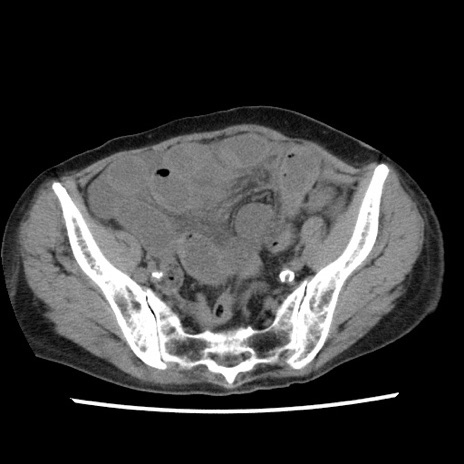

症例1(横断像)

【症例】80歳代女性

【主訴】腹痛

【現病歴】8時間前から腹痛あり来院。

【既往歴】糖尿病、脂質異常症、子宮体癌にて子宮全摘術

【身体所見】意識清明・会話良好だが腹痛で苦悶様、全腹部にわたって反跳痛と圧痛あり

【データ】WBC 13600、CRP 0.14、LDH 224、CK 90